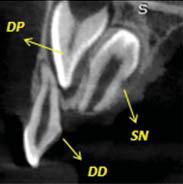

Con el fin de superar las deficiencias de la imagen en 2D, se han incrementado significativamente las solicitudes de tomografía computada de haz cónico (TCHC), siendo éste el estudio imagenológico ideal para la evaluación de los dientes SN (7).

La detección temprana de los dientes (SN) puede ser muy ventajosa para evitar futuras complicaciones. El tratamiento depende de la posición exacta, tamaño y tipo de SN, así como su repercusión sobre el diente temporal o permanente adyacente como reabsorción radicular externa, proximidad a estructuras anatómicas de importancia como el conducto dentario inferior, el conducto naso palatino, piso de las fosas nasales. La TCHC brinda toda esta información (8,9).